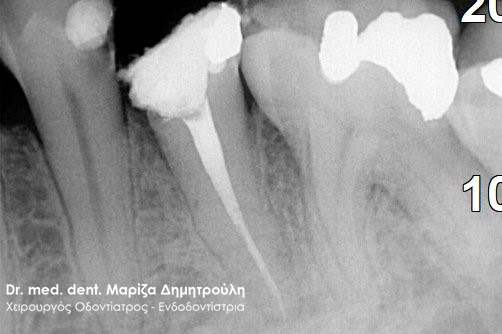

Ο ασθενής επισκέφτηκε το ιατρείο καθώς έσπασε ο άνω αριστερός προγόμφιος. Το συγκεκριμένο δόντι είχε μία παλία απονεύρωση δοντιού, η οποία περιοδικά έδινε συμπτώματα πόνου στον ασθενή. Μετά την κλινική και ακτινογραφική εξέταση του δοντιού αποφασίστηκε η επανάληψη της απονεύρωσης δοντιού και η προστασία του δοντιού με θήκη.

ΠΡΙΝ – Φωτογραφία πριν την αφαίρεση της παλιάς απονεύρωσης του δοντιού

Ακτινογραφική εικόνα του δοντιού πριν την επανάληψη της απονεύρωσης

Ακτινογραφική εικόνα του δοντιού μετά την επανάληψη της απονεύρωσης